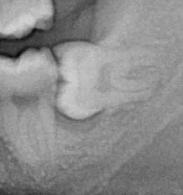

About a month after the extraction of my front tooth I noticed a big change in my health. I had a lot more energy than I used to, and when I did too much, it wasn't still effecting me days and days later. I clearly had found a large source of infection in my jaw. But this infection had been there for over a decade already, and had never been enough to bring down my health before. With my new energy I was able to take on more work, and I spent quite a lot of time my time helping my Dad on the farm, which is something I really enjoy doing. About 3 months later thought my health again started to deteriorate. The pain I was getting in the lymph nodes on the left side of my neck was getting really bad and my underarms were swelling up and the skin was pealing off. I immediately knew that I must have had an infection around my wisdom tooth, regardless of the advice the dentist had given me, so I set upon a quest to get that tooth removed. This proved to be a lot harder than I thought because most dentist won't touch horizontally impacted wisdom teeth. The dentist that had removed my front tooth, couldn't do it, but she kindly gave me a copy of my own x-ray, which is something my local dentist refused to do. It showed I had this problem.

The shadow area under the tooth is literally where infection has destroyed the bone. How my local dentist could think this is fine, I've no idea. The dentist that extracted my front tooth referred me to a dentist in Bristol, that she thought could extract my wisdom teeth. This dentist in Bristol had a unique perspective on dental problems as he had developed cavitations from poor extraction of his wisdom teeth, but also had a root canal next to the site of one of the cavitations. The infection in that area of his jaw had eaten a channel through his jawbone, almost killing him. One of his dentist friends did the surgery on him. Due to insurance reasons he couldn't operate on me though, which was just as well as I couldn't take someone seriously that tried to cast evil spirits out of me, even if he was genuine. (He opened the window to let them out.) I finally found a maxillofacial surgeon locally that I trusted enough to opperate on me. He told me he had stopped counting the number of wisdom teeth extractions he had done when he got to 10,000. I asked him if he had ever heard of cavitations, and he hadn't. So I printed just about everything on the subject I could find on it and asked him to read it. He did. He was pretty shocked at what he read and happily went along with the changes I suggested, which was to remove the peridontal ligaments and thoroughly clean the socket. When I had the surgery, he removed the tooth and found quite a lot of mushy infected bone under the tooth. He cut it out and showed it to me. He did his best to clean the socket, scrape out the ligaments and stitched me up. Because I didn't have much gum around that wisdom tooth I was left with an open hole, for virtually 4 months. The dentist packed it with a sort of wool packed with oil of cloves. A month or two after surger, again I noticed a difference in my health. This time it was a big difference, for the first time in literally years, my sore throat went, no more swelling in my underarms. My health had really returned to me, it was fantastic. When the hole finally healed up, I got my other horizontally impacted wisdom tooth removed. For a while, everything seemed good.